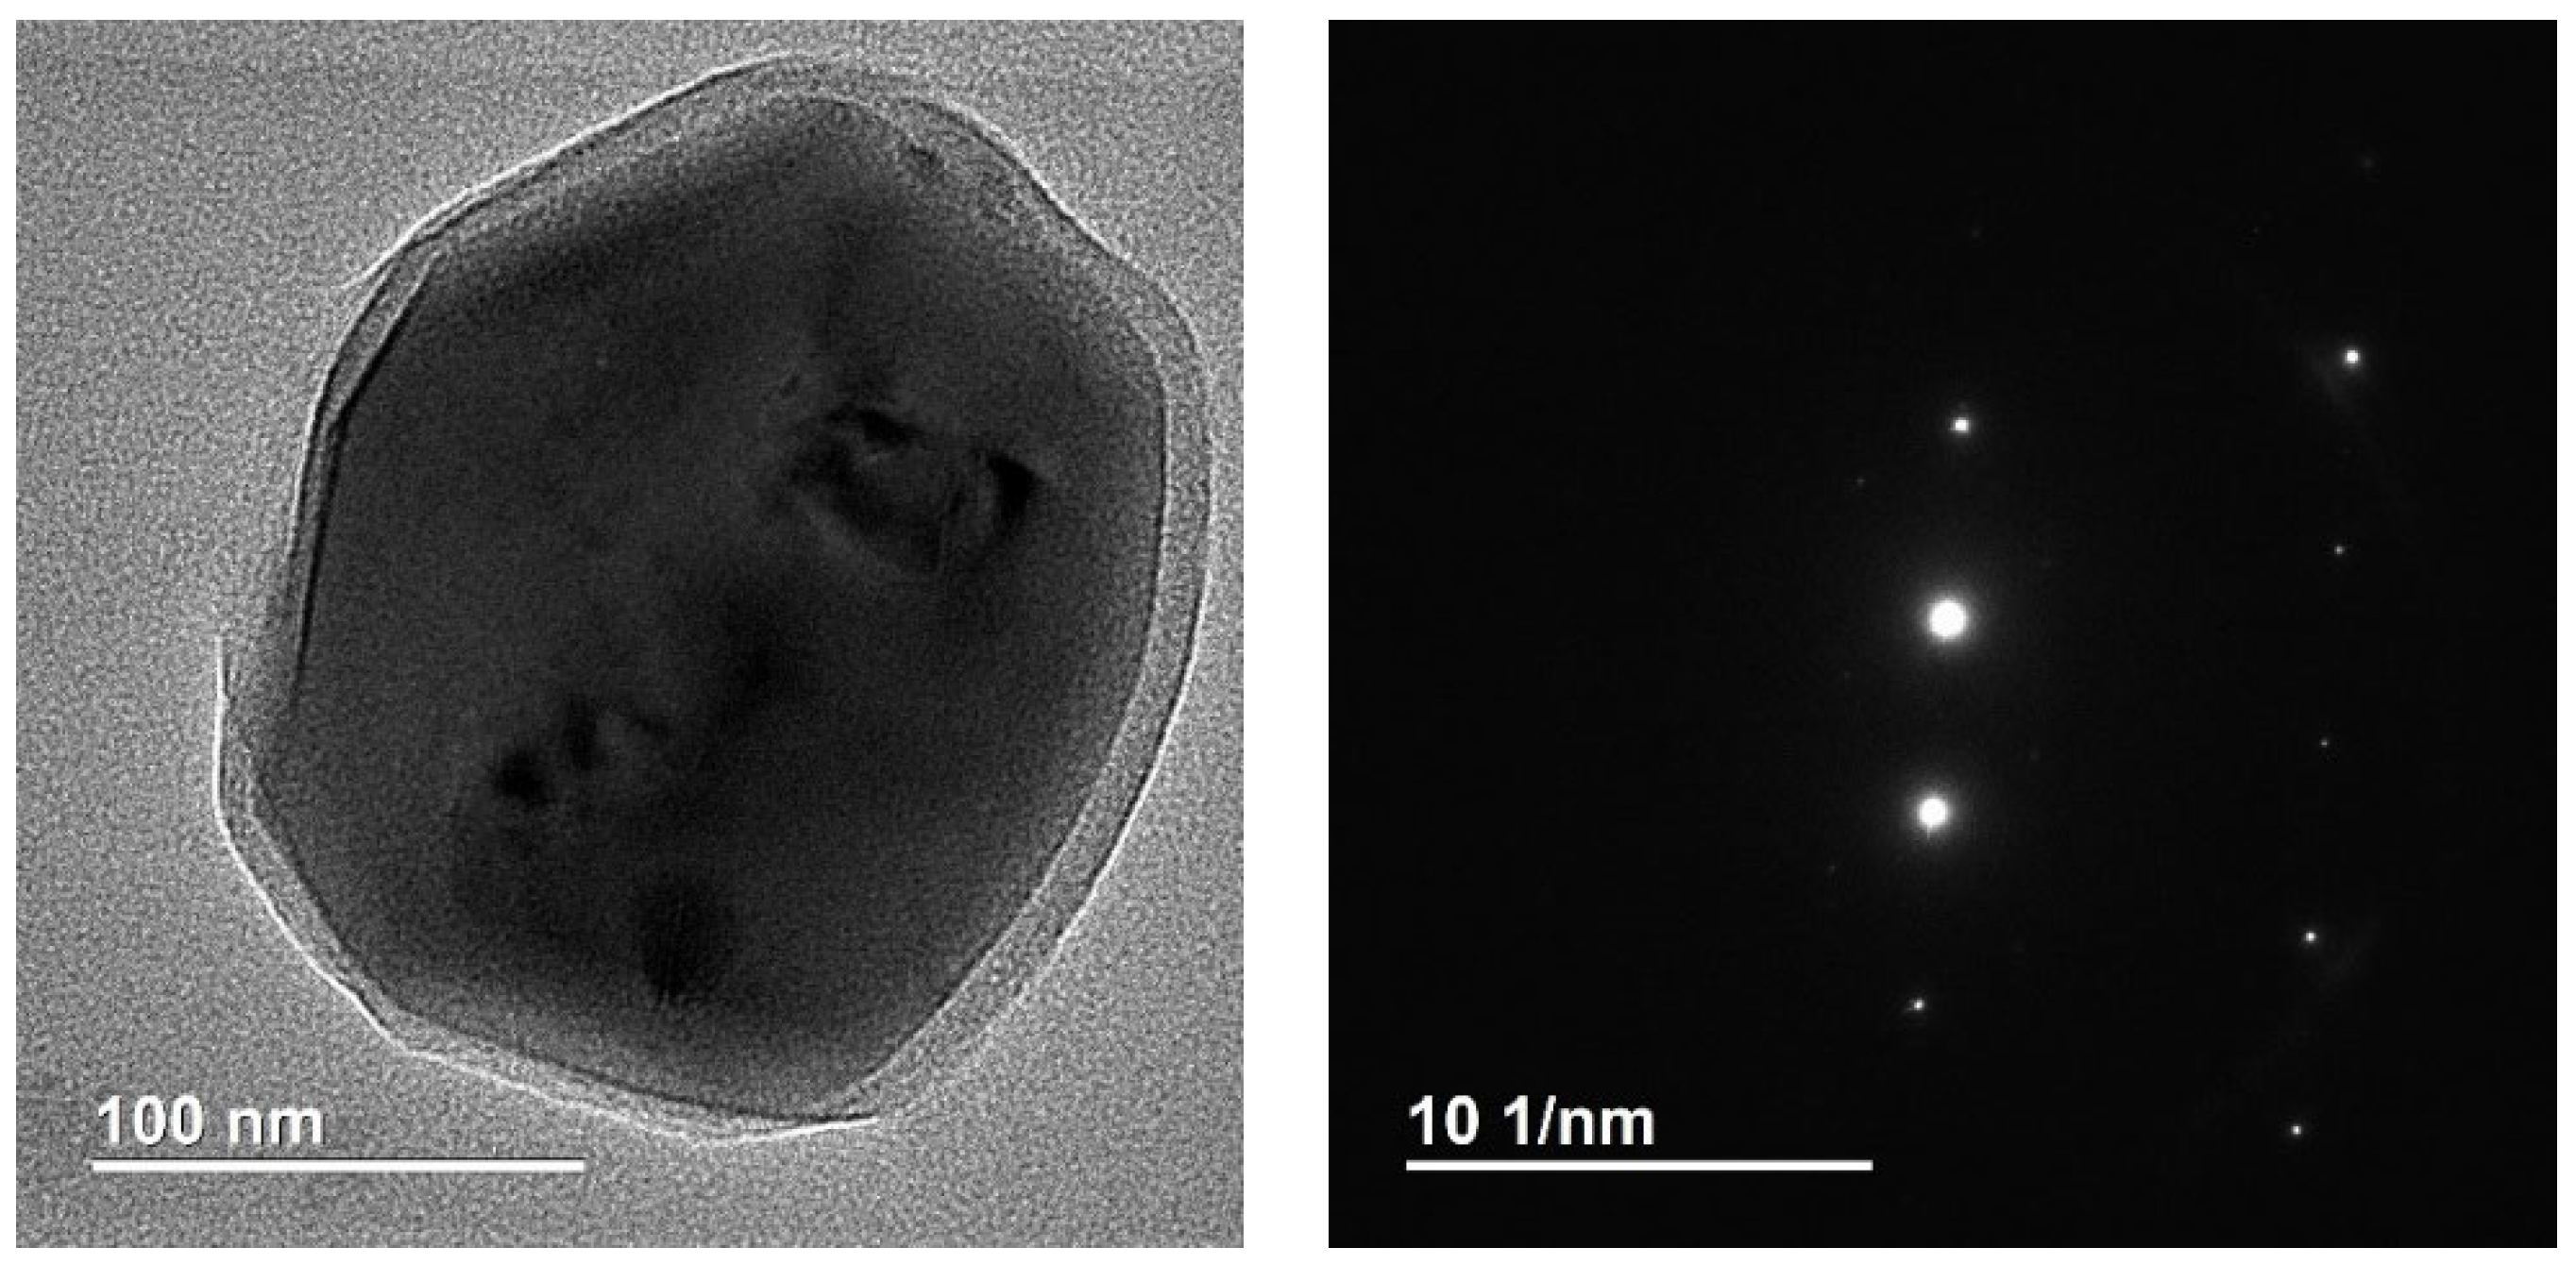

4.4. Methods of Scanning Electron Microscopy (SEM) and Transmission Electron Microscopy (TEM) with Energy Dispersive (ED) Analysis

2.1.1. Results of X-ray and Electron Microscopic Studies